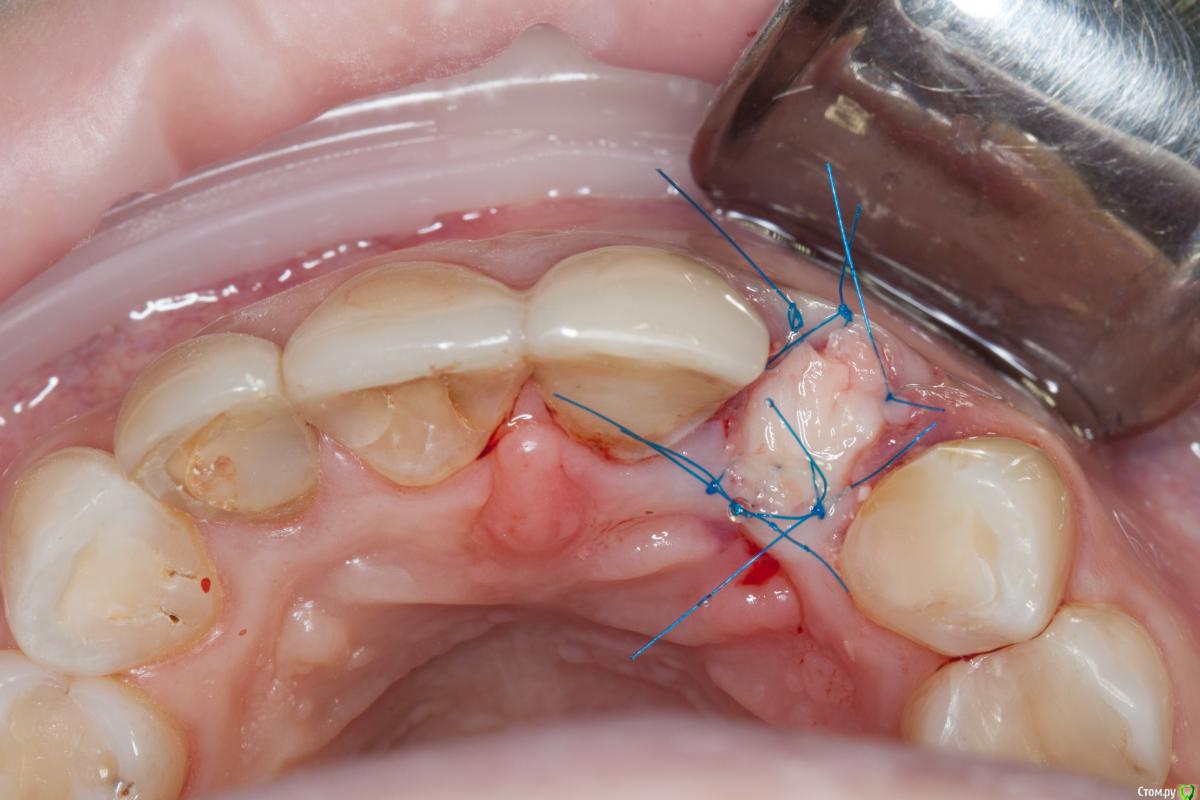

Популярный пост ILGAMSA Опубликовано 16 марта, 2015 Популярный пост Поделиться Опубликовано 16 марта, 2015 Был задан вопрос вот здесь http://forum.stom.ru/topic/24739-implantat-36-sst/page-2 Отвечаю http://s020.radikal.ru/i708/1503/88/3216c8c6ab83.jpg лунка замещена БиоОсс, перекрыта мембраной, на лунку перекинут соединительно-тканный трансплантат на питающей ножке Через полгода http://s017.radikal.ru/i419/1503/46/55d1baef6dc7.jpg небольшой дефицит с небной стороны отростка обусловлен частичным отсутствием небной стенки альвеолы. Не критично. Такие дела... 24 Ссылка на комментарий